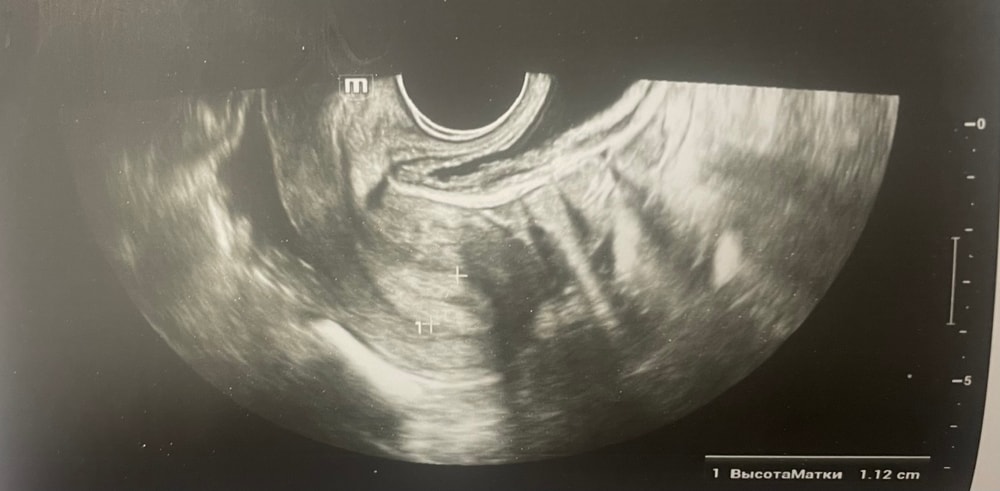

УЗИДобрый день, мы с мужем планируем беременность и в этом месяце произошло что то странное… дата начала последней менструации 4 октября закончилась 8, овуляцию отслеживала всю неделю почти сначала были бледные еле заметные полоски, 23 октября жирные четкие полоски, 24 октября стала чуть бледнее но яркая, вообщем положительный ещё был, с 25 числа тест уже отрицательный, через день после овуляции 26 числа стала странно себя чувствовать и во время овуляции болел живот то справа то с лева и поясница, так через день после начали болеть соски грудь вообще не болела, живот то болит то нет и с поясницей также, позже появилась небольшая изжога, нога немеет правая не знаю с чем связано), все это началось за 2 недели до месячных в середине цикла скажем так 29 числа пошла на узи спустя 6 дней грубо говоря гиня сказала что у меня была очень хорошая овуляция, что её признаки сохраняются до сих пор так скажем, желтое тело СПРАВО 20 мм, мои симптомы и все это очень похоже на беременность сказали большая вероятность, я очень была рада и надеялась, после узи появились выделения с комочками, до этого были просто густые белые выделения, утром тоже самое, пошла опять к гинекологу она сказала это может быть при ранец беременности сказала какие свечи купить, вечером я попала в не большое ДТП, удар был в поясницу и копчик, живот начал тянуть и поясница сильно болеть, начала болеть сама грудь помимо сосков, живот прошел относительно быстро, а вот поясница ломит до сих пор, решила сходить ещё раз на узи очень испугалась, на узи я пошла 31 через два дня после предыдущего и уже к другому гинекологу, моя на больничном, она сказала, что у меня отсутствуют даже косвенные признаки беременности и желтое тело с ЛЕВО А НЕ С ПРАВО, я не понимаю как такое может быть, очень расстроилась и совсем забыла про фото узи, она мне его не дала только заключение и как выяснилось уже не дадут оно не сохранилось, сказали переделывать, я очень доверяю своему гинекологу, но по заключению второго врача о беременности не может быть и речи в этом цикле, я не понимаю как желтое тело оказалось с лево если оно точно было справа в этом я уверена, а вторая врач уверяет во Братном, живот в обуляцию хоть и болел с двух сторон но больше справа помойму, вообщем я не понимаю есть ли шанс что я беременна или все таки нет, я понимаю что это слишком рано, до задержки ещё 4 дня, но мне плохо уже неделю по симптомам даже больше это же не просто так, я прикреплю фото заключения, могу ли я быть беременна, если посмотреть на эти заключения хотябы, подскажите пожалуйста фото узи относятся к 29.10, без фото 31.10